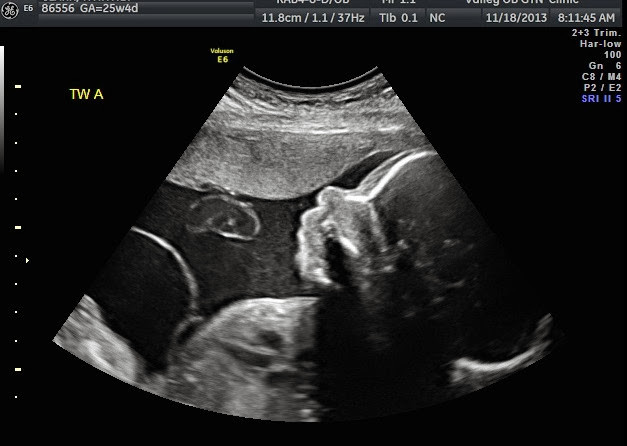

We are 25w4d today and doing very well! We had an OB appointment and ultrasound today. The ultrasound was primarily to check for cervical length. This is done because the cervix is essentially the "plug" that keeps the babies inside and baking. A "good" cervical length is anything > 3cm. We will check it quite frequently as time goes on as this is an early indicator of preterm labor. Today cervical length was 3.8cm so yay!!

Even though we only went for a cervical length check, the ultrasound tech did take time to look at our "too cute" kids! She even got a bunch of 3D pics for us!!

Baby A Profile

Baby A lower leg and foot

Baby A foot

Baby B heart rate (she was doing calisthenics!)

Baby B foot